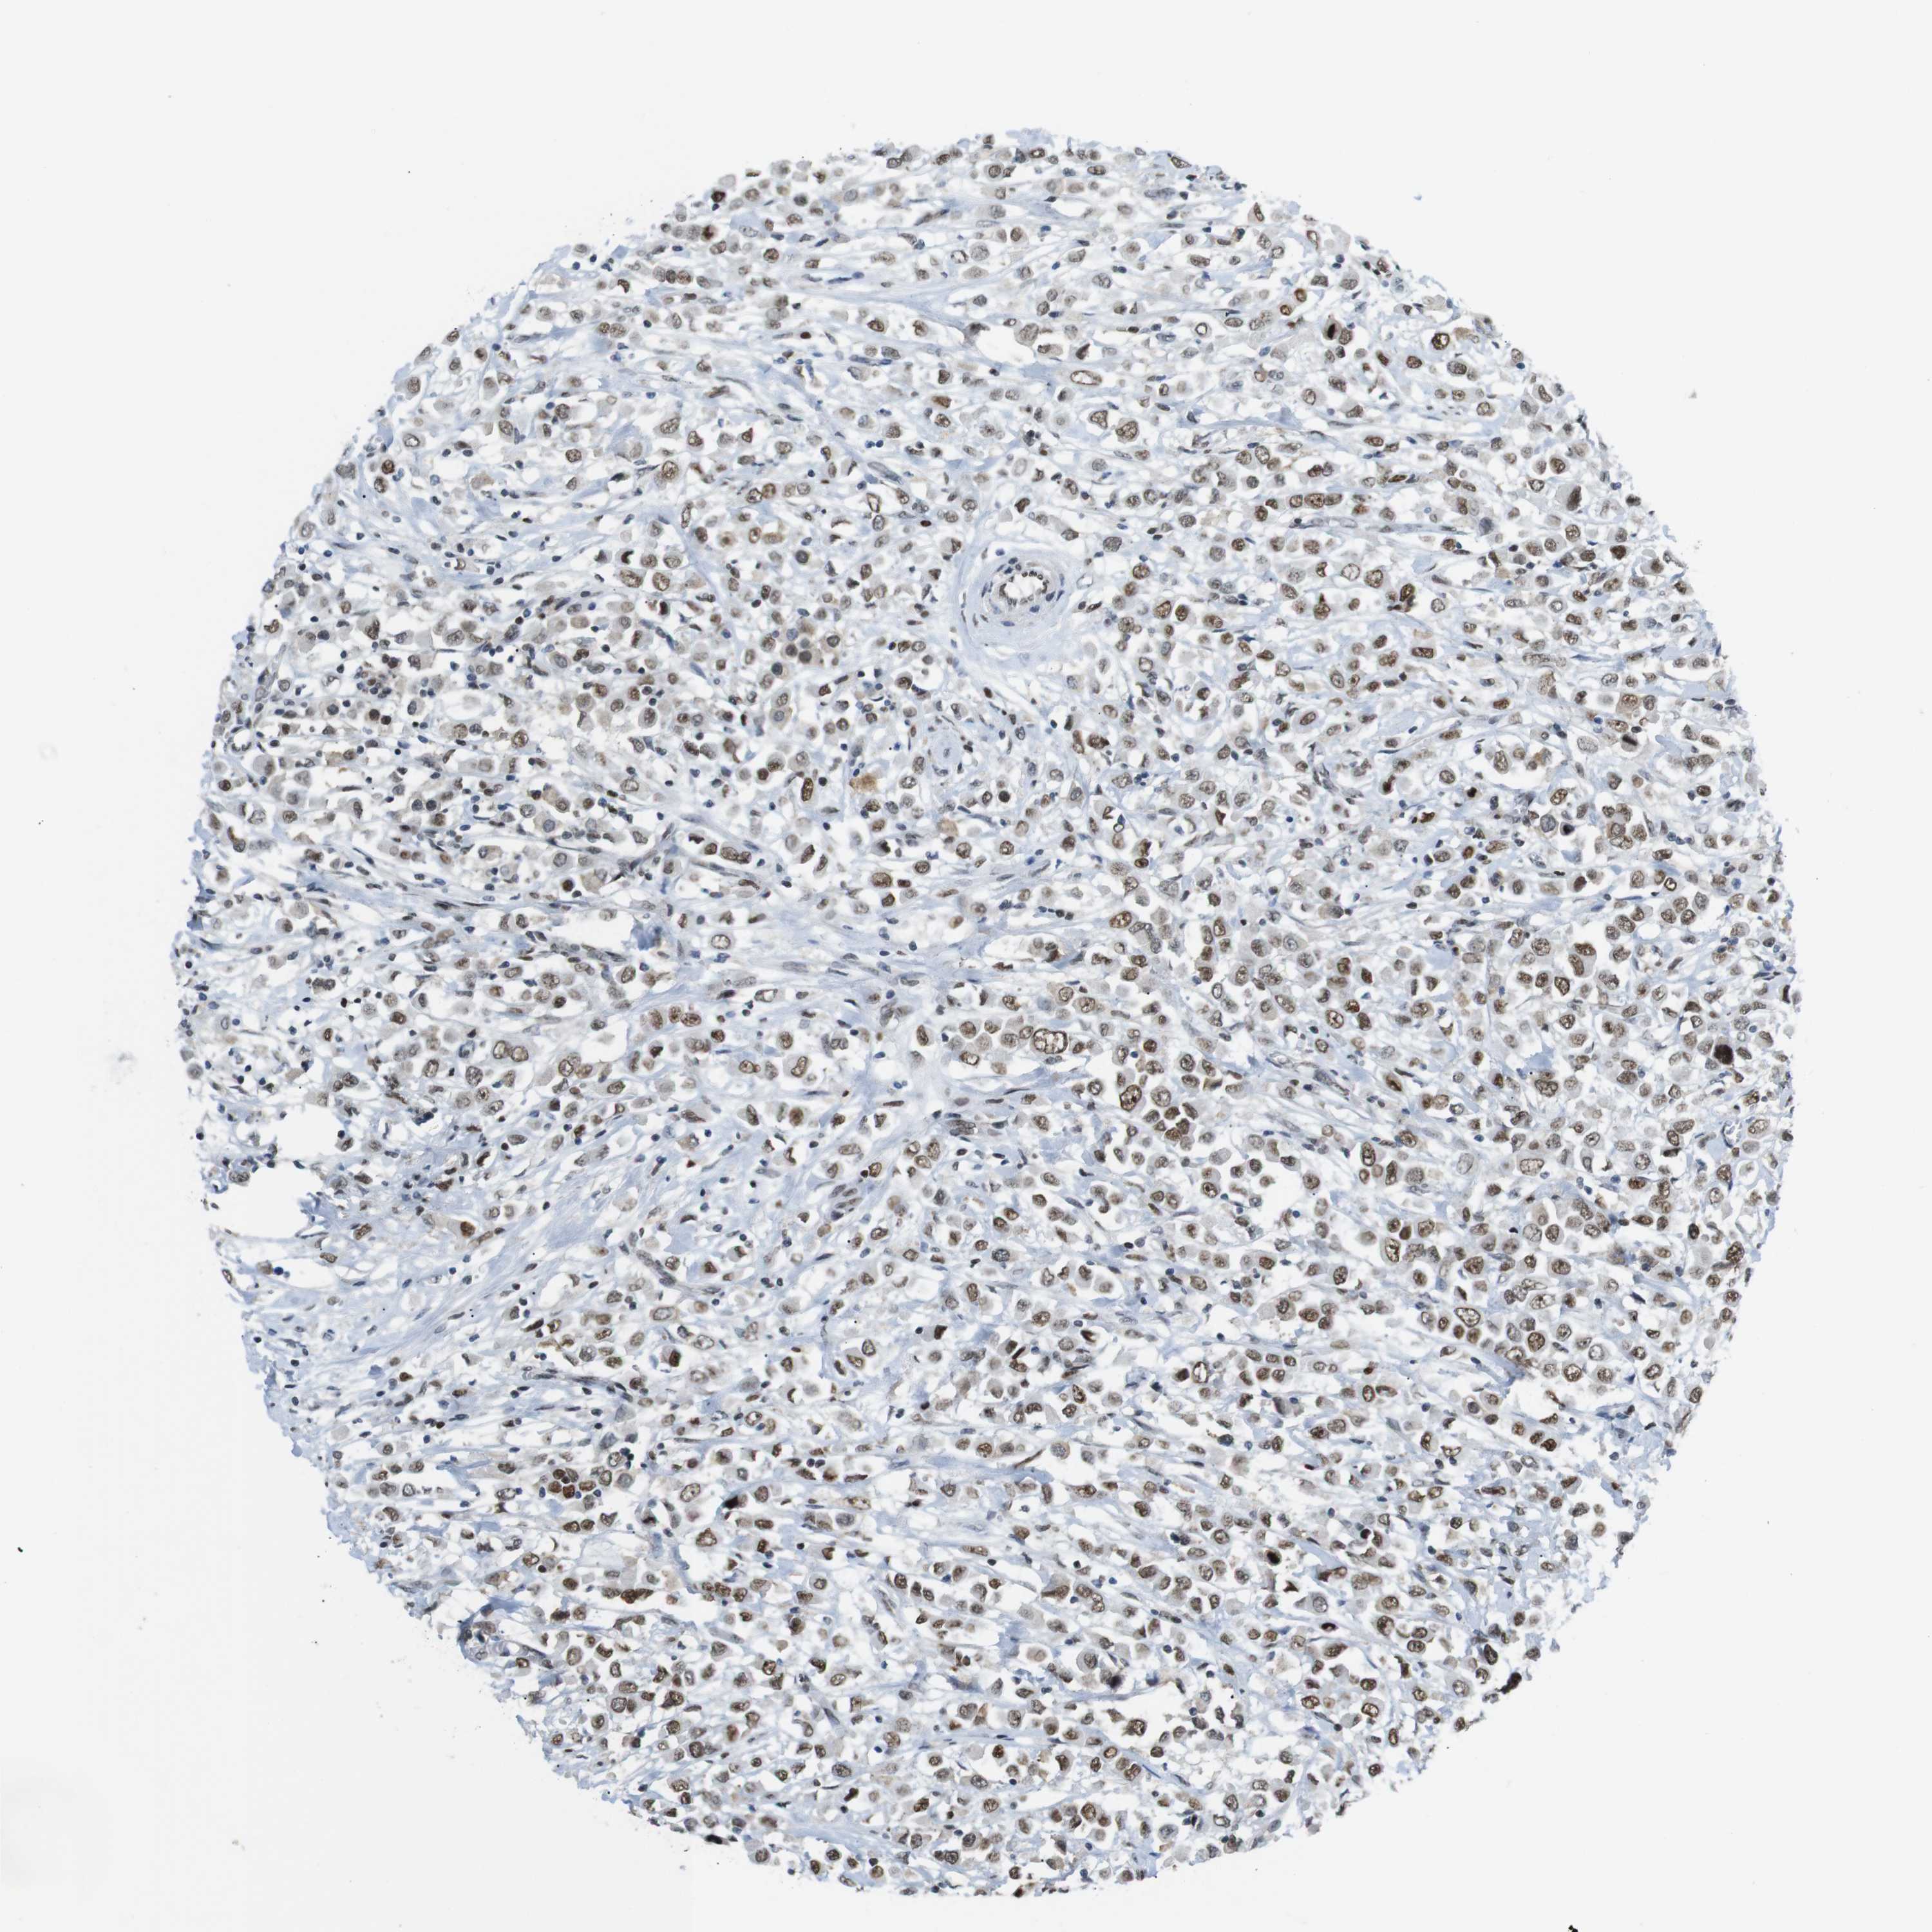

BRCA TCGA BRCA VALIDATION PROTEIN EXPRESSION